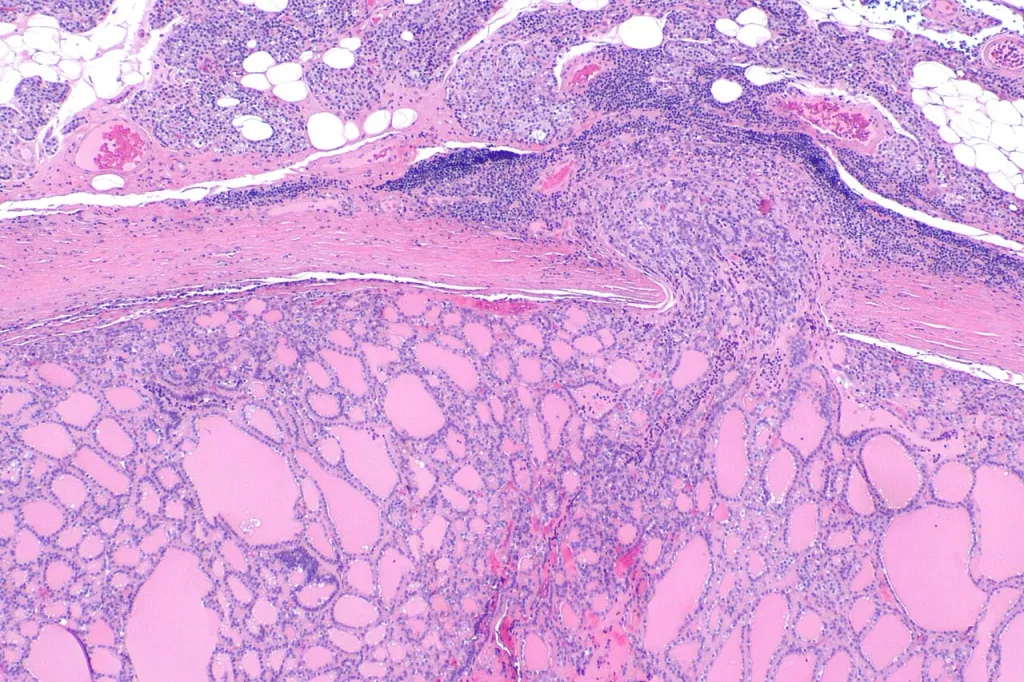

പത്തോളജി പരിശോധന

നമ്മുടെ ശരീരത്തിൽനിന്ന് തൈറോയ്ഡ് നീക്കം ചെയ്താൽ അതൊരു പത്തോളജിസ്റ്റ് പരിശോധിച്ച് അത് ക്യാൻസറാണോ സാധാരണ മുഴയാണോ എന്ന് ഉറപ്പുവരുത്തണം. സാധാരണയായി തൈറോയ്ഡുകൾ നീക്കം ചെയ്യുന്നതിനായി സർജനെയോ എൻഡോക്രൈൻ സർജനെയോ ഓങ്കോ സർജനെയോ സമീപിക്കാവുന്നതാണ്.